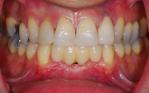

Replacement of all four failing lower front teeth with an implant bridge, some whitening, composite bondings and one new crown on an upper lateral incisor